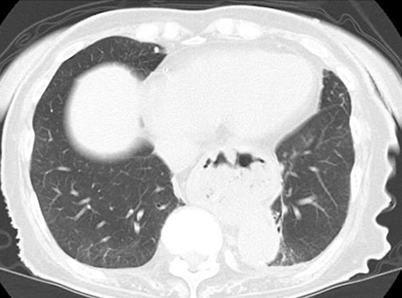

CTで確認すると食道内に胃があることが確認できます。